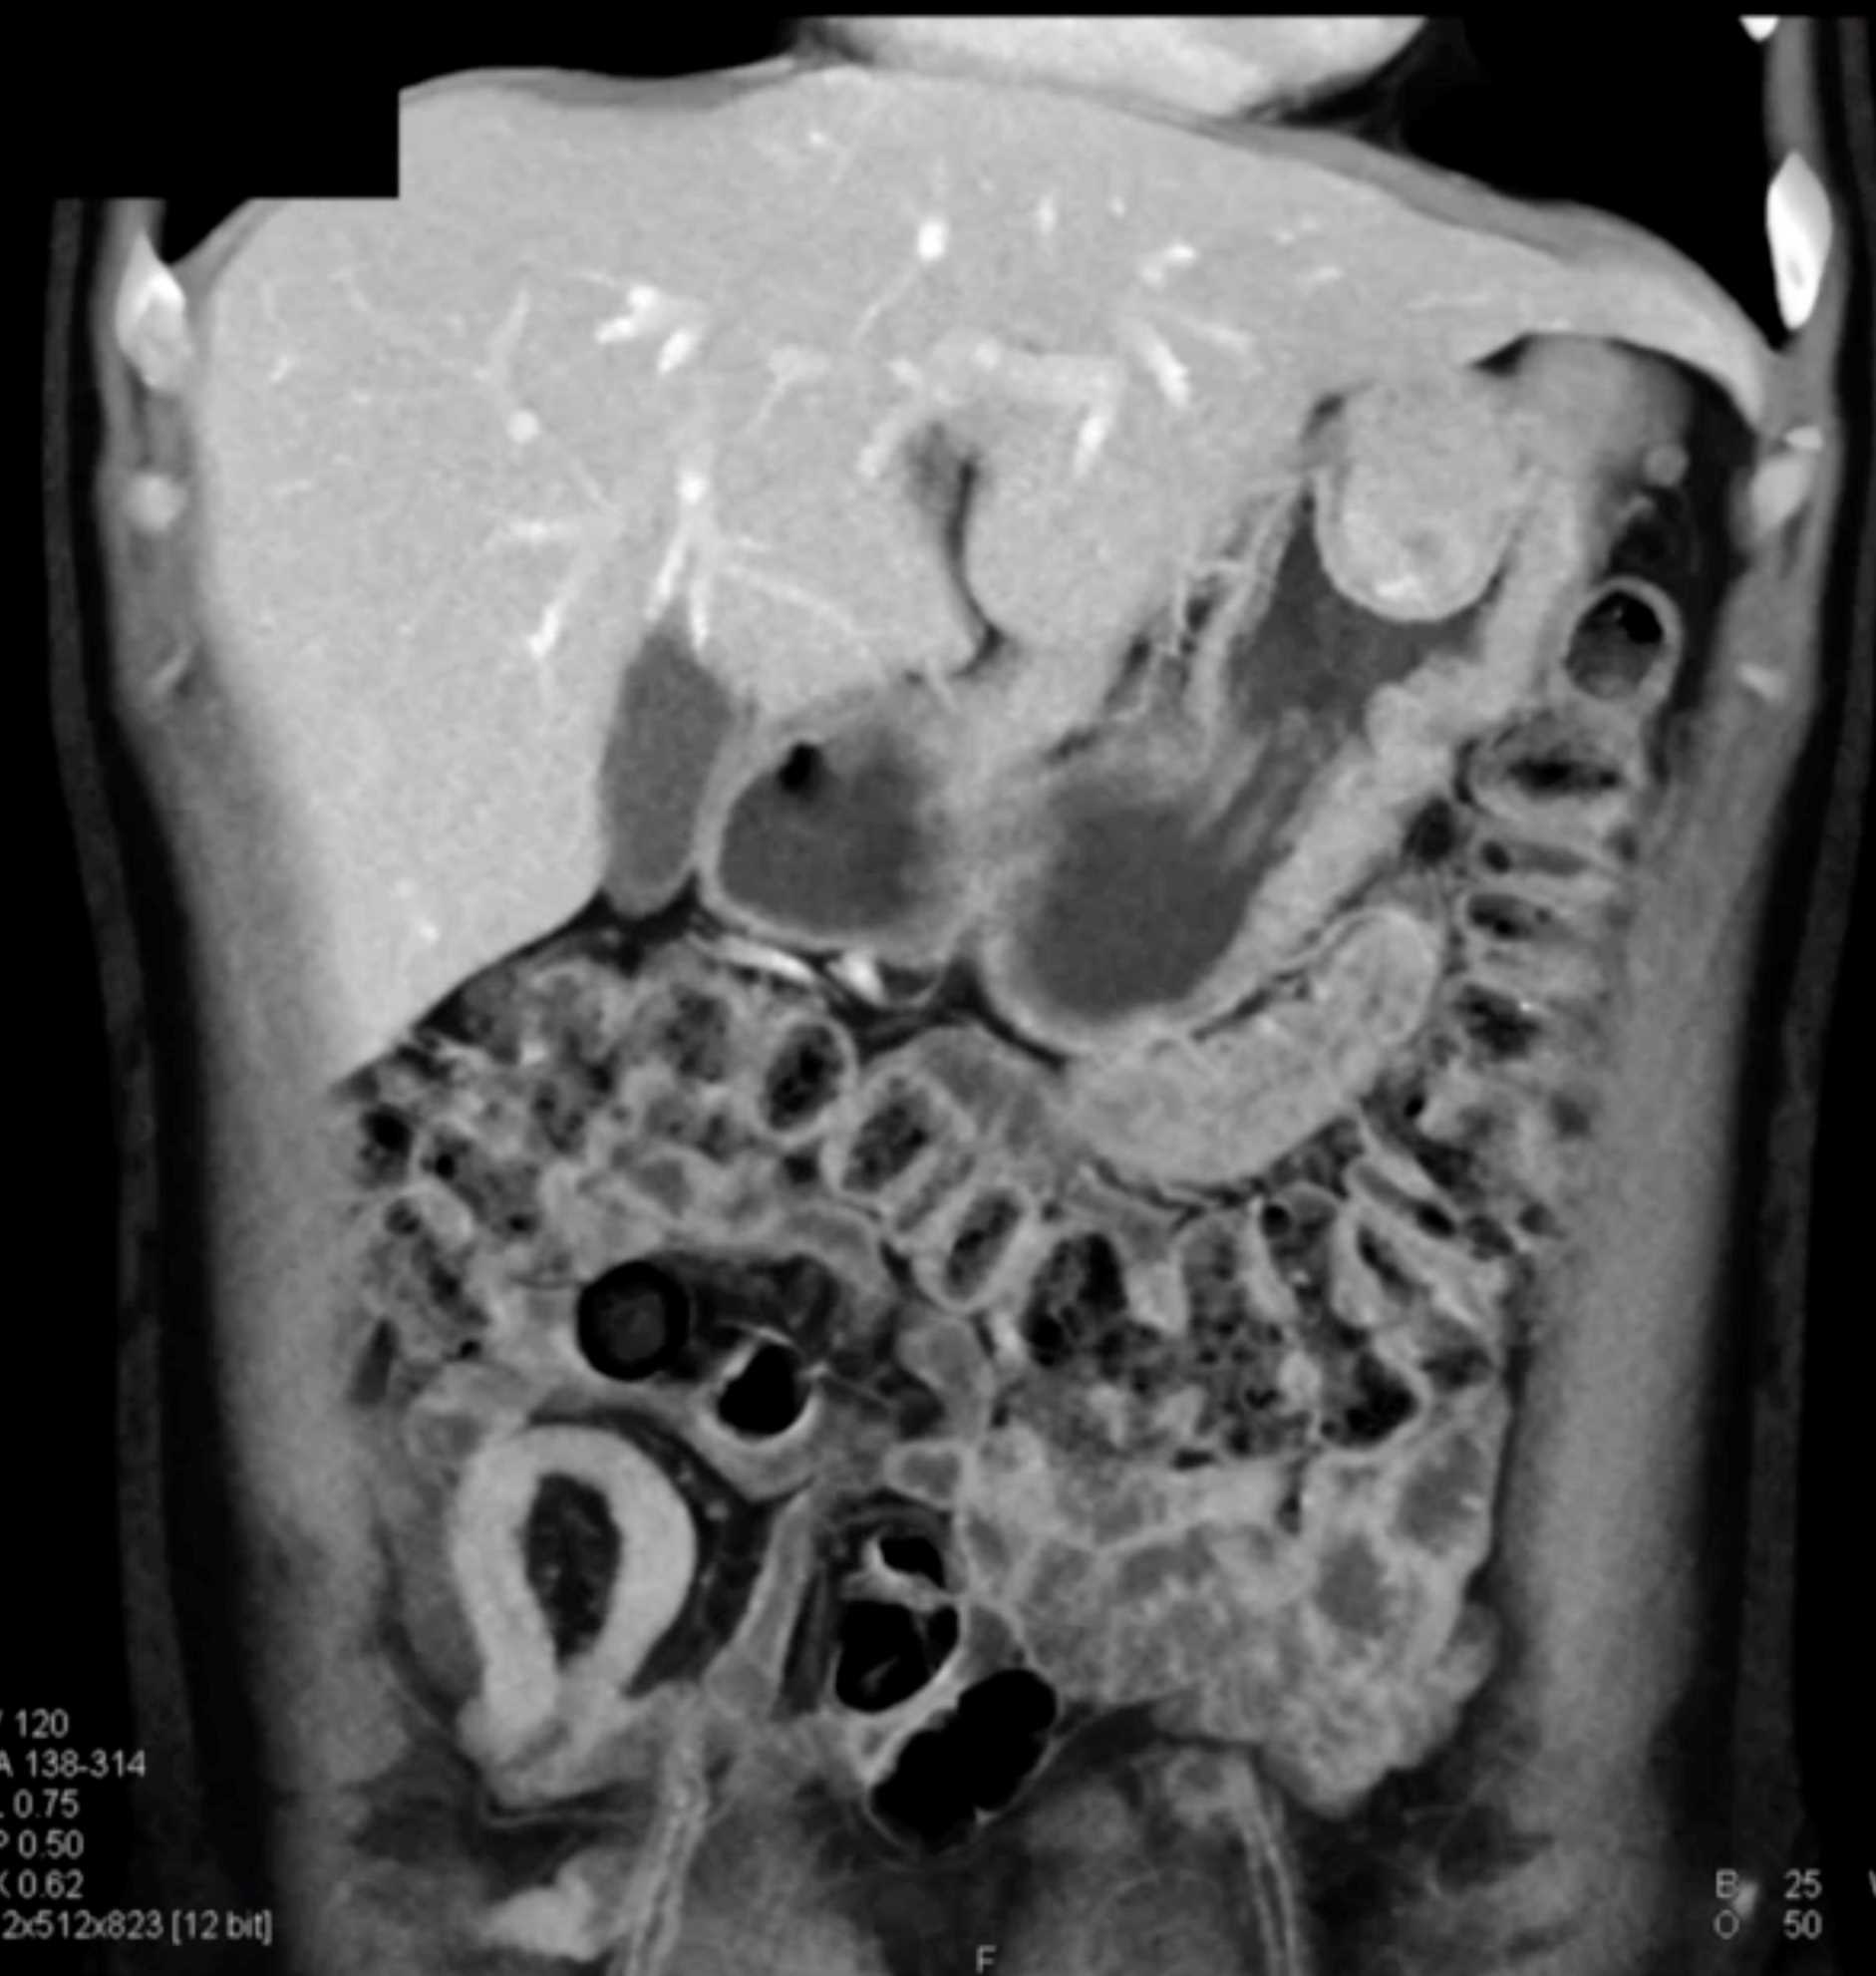

Multiple Gastric GIST Tumors with Spread to Nodes (Carney-Stratakis Syndrome)